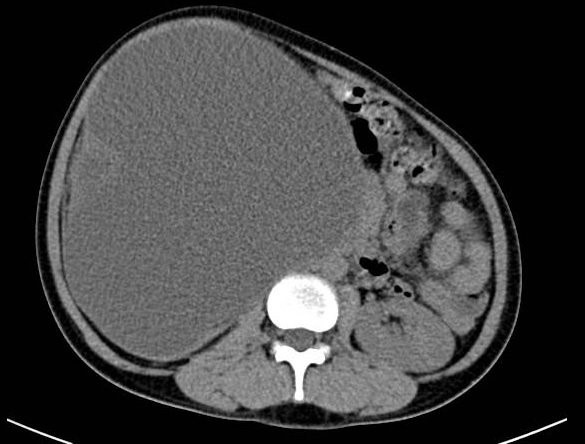

Hình ảnh cắt lớp vi tính của bệnh nhân trước khi phẫu thuật

Qua quá trình thăm khám kết hợp với kết quả xét nghiệm, siêu âm và chụp cắt lớp vi tính ổ bụng, các bác sĩ phát hiện thận bệnh nhân bị ứ nước độ 4 do sỏi niệu quản (nhu mô thận chỉ còn như tờ giấy) kèm theo triệu chứng nhiễm trùng. Bệnh nhân M. được chẩn đoán thận phải ứ mủ độ 4, mất chức năng.